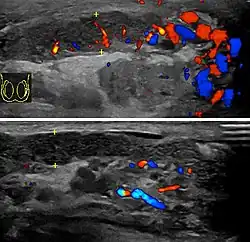

Epididymitis usually has a gradual onset. Typical findings are redness, warmth, and swelling of the scrotum, with tenderness behind the testicle, away from the middle (this is the normal position of the epididymis relative to the testicle). The cremasteric reflex (elevation of the testicle in response to stroking the upper inner thigh) remains normal.[1] This is a useful sign to distinguish it from testicular torsion. If there is pain relieved by elevation of the testicle, this is called Prehn's sign, which is, however, non-specific and is not useful for diagnosis.[13] Before the advent of sophisticated medical imaging techniques, surgical exploration was the standard of care. Today, Doppler ultrasound is a common test: it can demonstrate areas of blood flow and can distinguish clearly between epididymitis and torsion. However, as torsion and other sources of testicular pain can often be determined by palpation alone, some studies have suggested that the only real benefit of an ultrasound is to assure the person that they do not have testicular cancer.[14]: p.237 Nuclear testicular blood flow testing is rarely used.